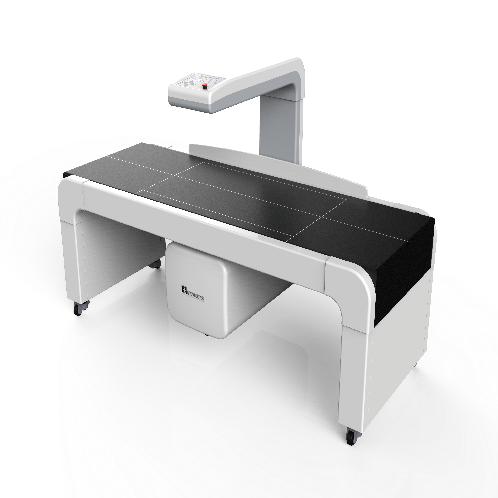

Model InAlyzer AIRMEDIKORS

1850*800*1162 mm/ 138 kg

64 channel DXA Bone Densitometry

InAlyzer AIR uses 64 ch dual energy x-ray detector based on Fan Beam technology and obtains 64 rows of data per one x-ray irradiation, enabling acquisition of data of higher resolution in a shorter time, unlike pencil beam system that obtains 1 row of data per one x ray irradiation. Also the reliability and durability was enhanced by using an x ray generator that does not require fast switching between high energy and low energy, and the x ray detector that acquires high resolution data of high energy and low energy independently provides high-quality images.

InAlyzer AIR has an open design for the first time in the world, and this results in not only a chic design but also, by locating the moving axis to the center of the moving part, minimizing the shaking between the X ray generation and x ray detection section during the scan and, thereby, maintaining accuracy in the measurement result.

1. High resolution and fast measurement

By applying the energy-fixed x-ray generator, we minimized the failure rate, while the energy-independent high-resolution detector provides fast high resolution results.

2. Wide inside & Compact outside

Our own equipment technology maximized the scan are, minimizing the patient's movement and external size for space efficiency in hospitals.

4. Excellent & Robust design

As a product of a national R&D project, the equipment features a chic design, including the world-first open of its kind, reduced rate of errors caused by vibration during scanning, and therefore, high levels of accuracy and precision.